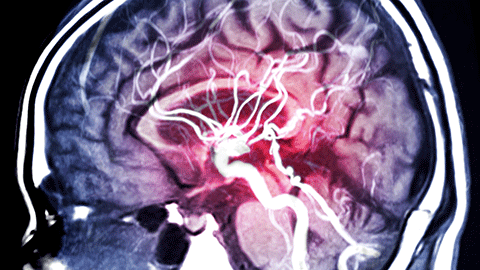

Illustration of a brain scan during a stroke

02:54 RW: So a stroke is the result of something bad happening inside the central nervous system. Usually we talk about this happening in the brain, but there is such a thing as spinal cord stroke as well. There are sort of two different versions or types of stroke. One has to do with a blockage, and the other has to do with a bleed. The blockage type, called ischemic strokes, are much more common and so there's a clot or some debris that gets into a small artery or arterial inside the brain, blocks blood flow and then the tissue downstream from that dies, and that's called an ischemic stroke. When we have a hemorrhagic stroke, then there is an event where there is a burst, an artery ruptures, and again, all the material downstream that should have been supplied by that blood vessel will now suffer from lack of oxygen. But again, ischemic strokes are by far the more common version in the United States.